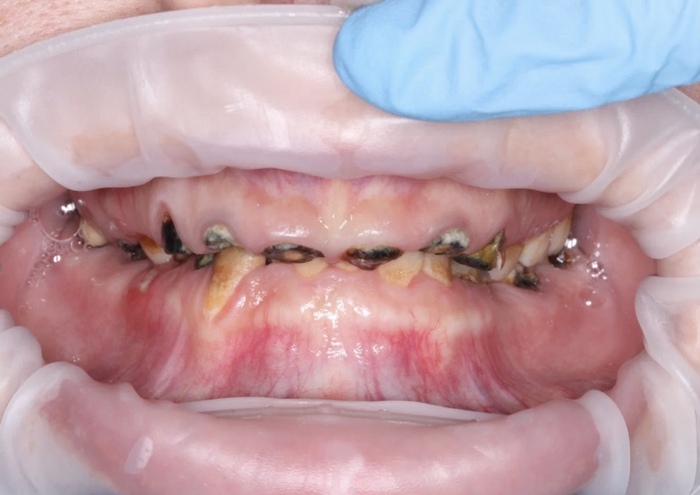

Вот так выглядело до удаления в начале пути после спиливания неудачных имплантов :

Вот так перед этой самой операцией: